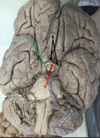

1. Identify the highlighted (red) area. 2. What structure is the black arrow pointing to? 3. What structure is the blue arrow pointing to? 4. What structure is the green arrow pointing to?

1. Occipitotemporal Sulcus 2. Parahippocampal Gyrus/ uncus 3. Medial Occipitotemporal gyrus 4. Lateral Occipitotemporal gyrus